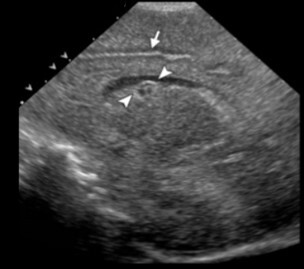

Neonatology Subependymal Cyst Image